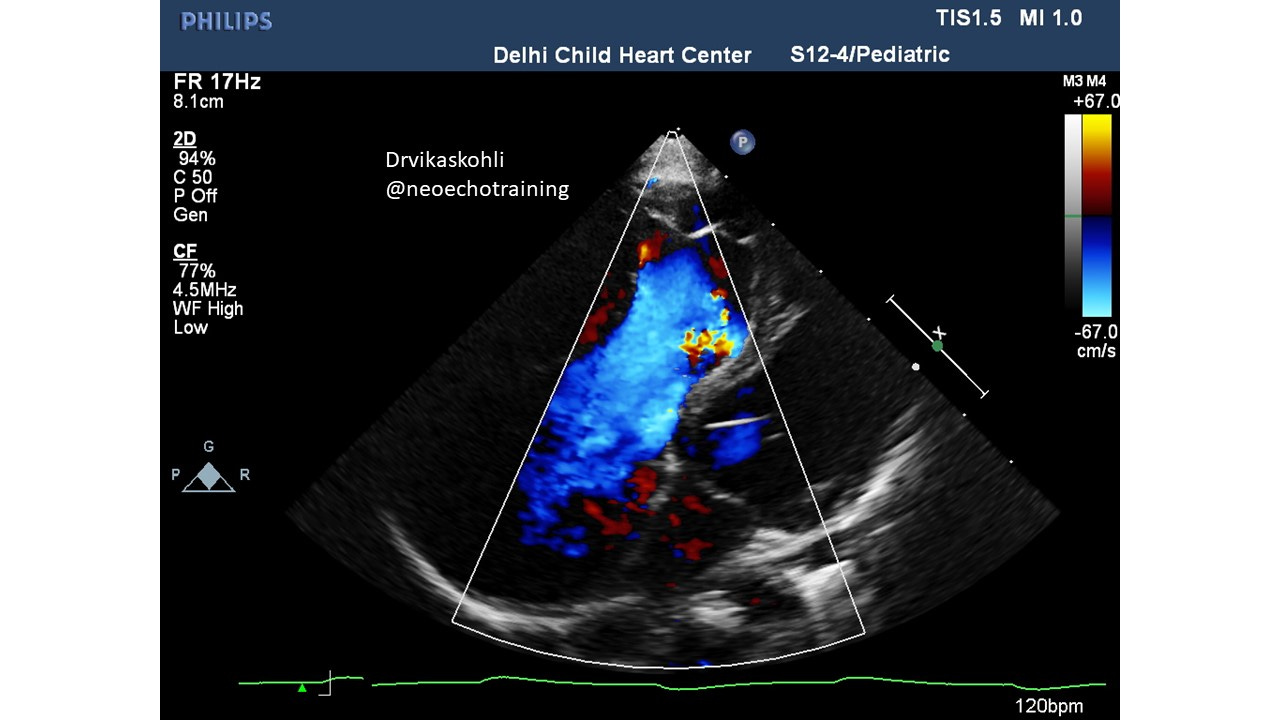

a). The Tricuspid Leaflets are HUGE

b). The leaflets are seen septal (along the septum and the Anterior which is along the free wall).

This is associated with severe TR which is normal pressure TR.